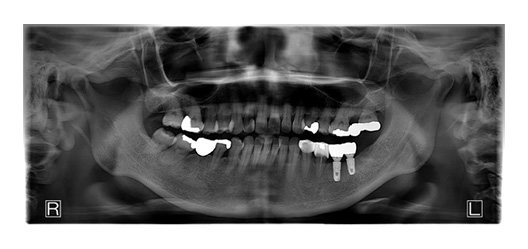

CASE_03

40代女性(インプラント)

- 患者さん情報(年齢・性別)

- 40代 女性

- 主訴

- 被せものをインプラントにしたい

- 治療箇所

- 2箇所

- 治療方法

- インプラント

- 費用

- 84万円

- 治療期間

- 約半年

- その治療によるリスク・副作用

-

- 治療期間がながい、外科的治療が必要